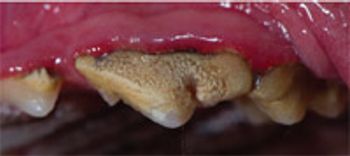

The degree of severity of periodontal disease relates to a single tooth; a patient may have teeth that have different stages of periodontal disease. Here is an outline of the American Veterinary Dental College-approved periodontal disease classifications.